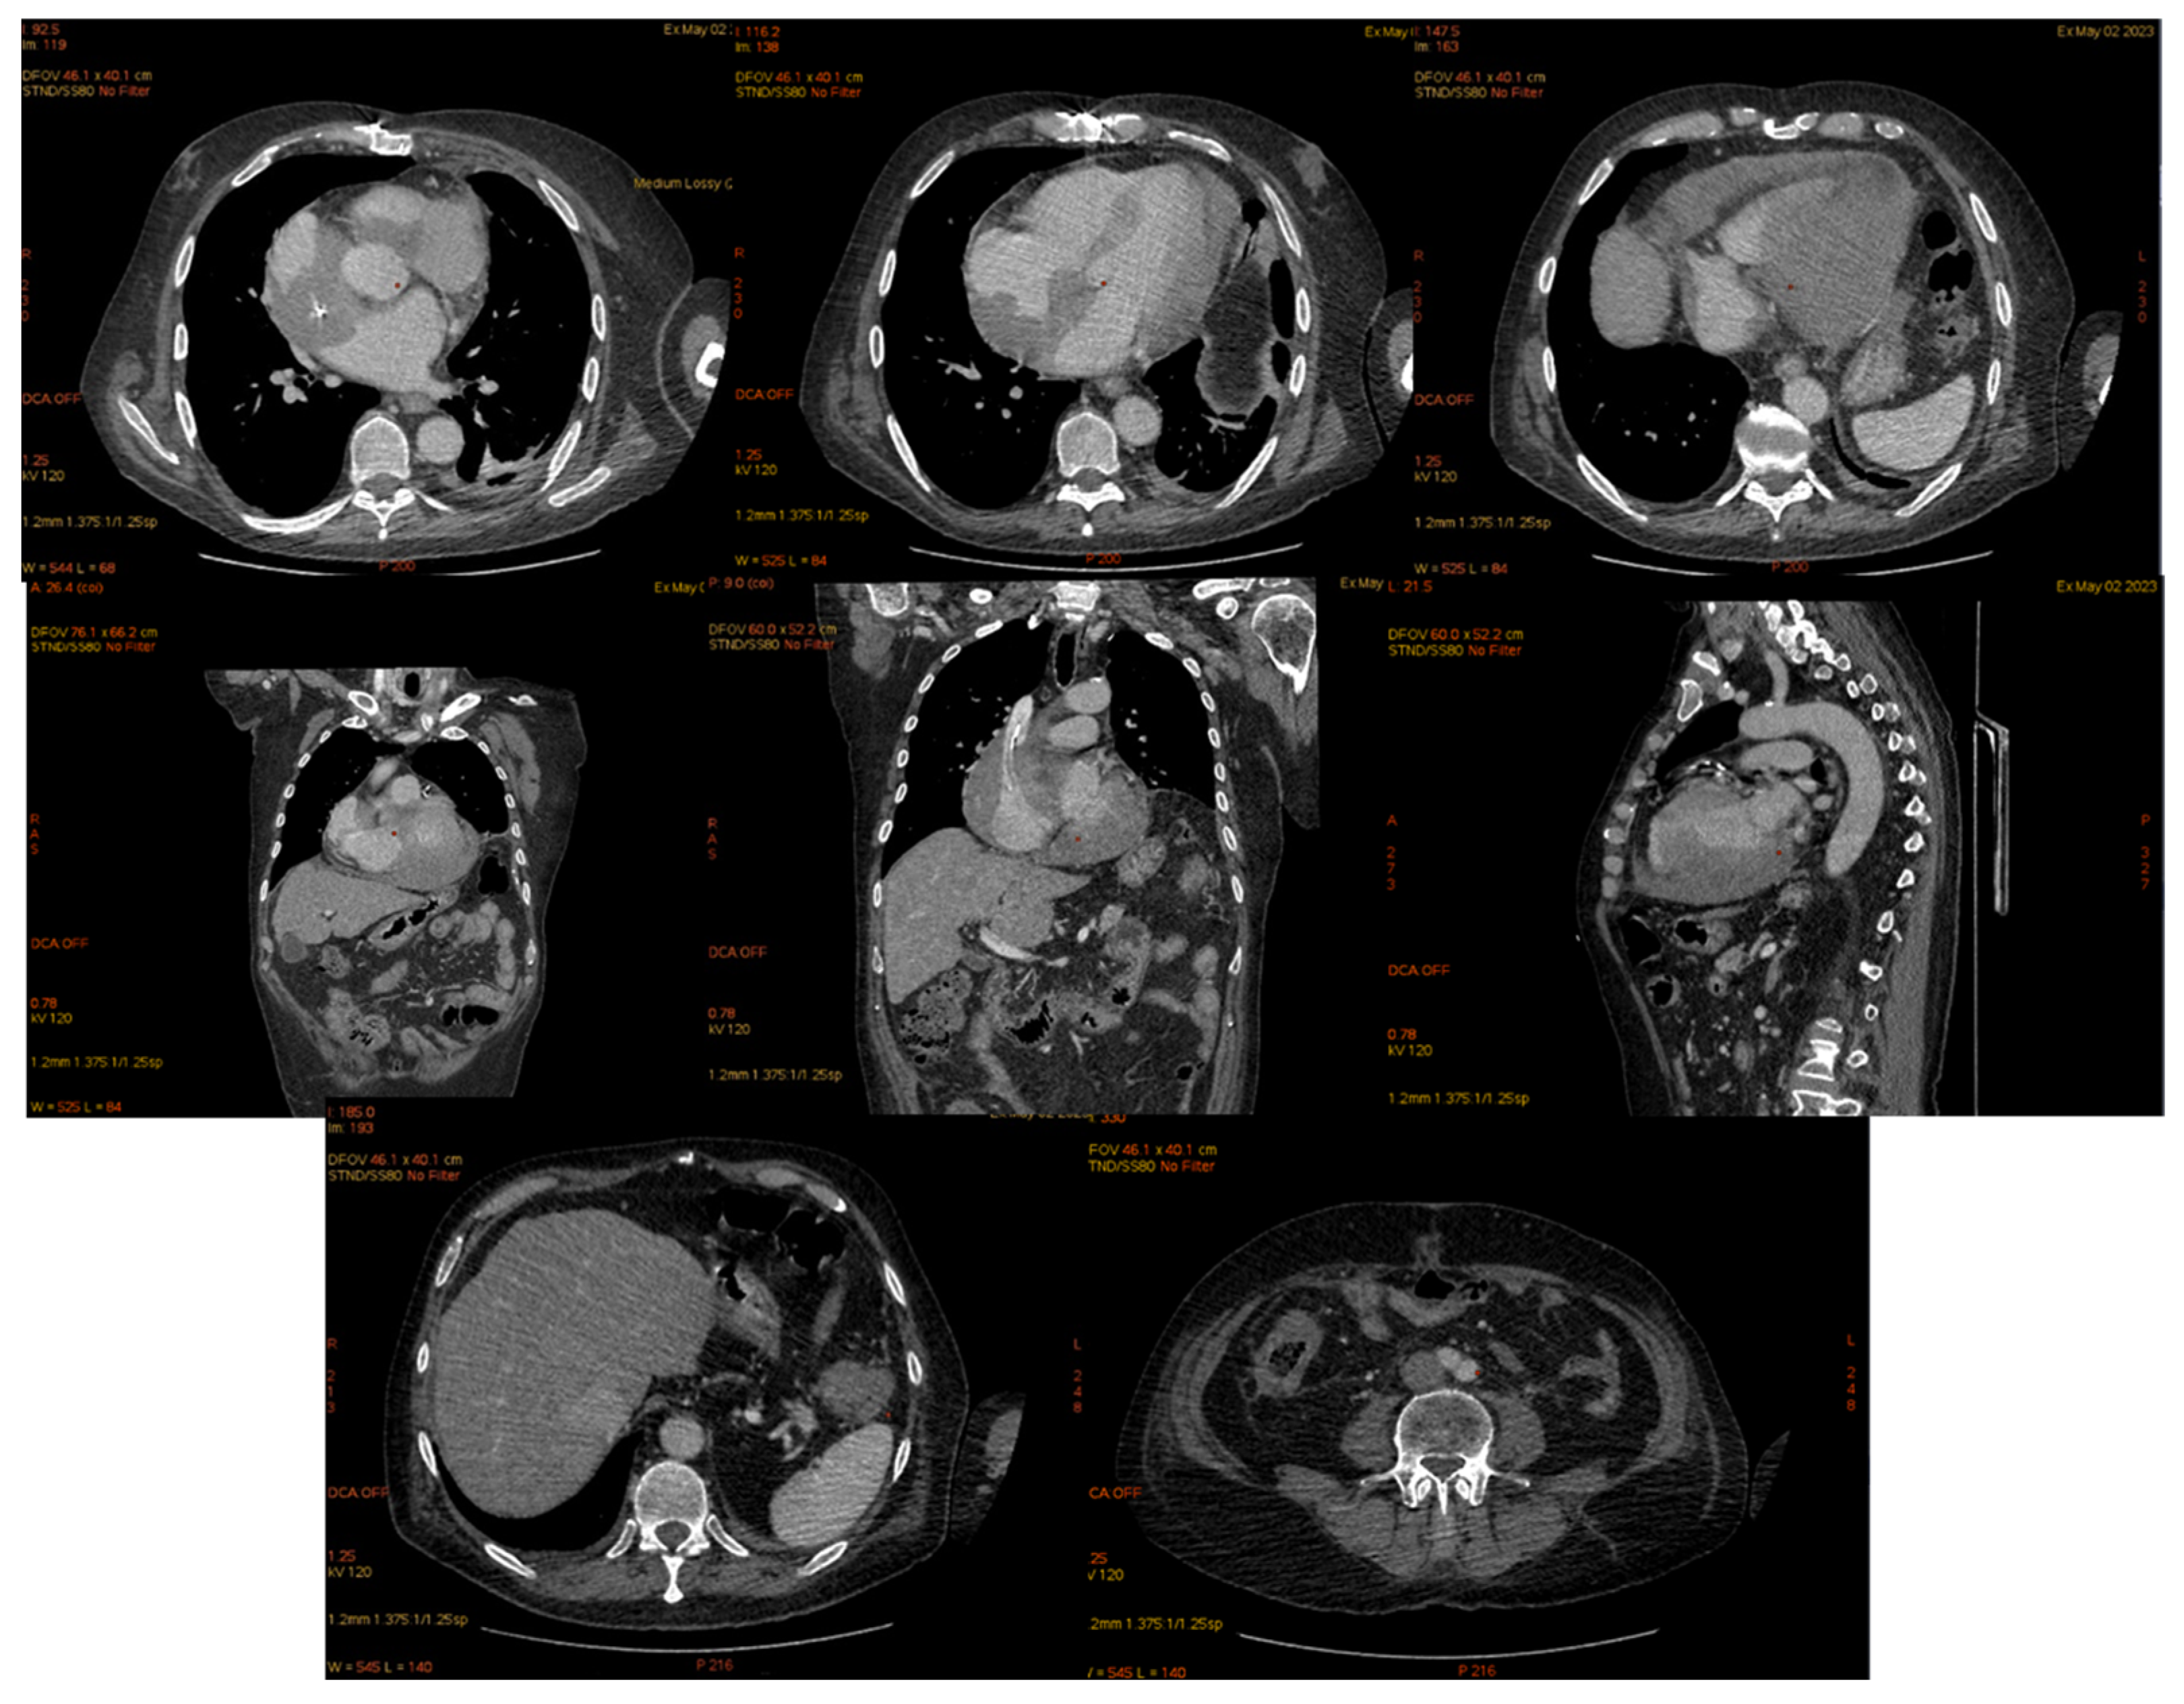

| 2 May 2023 | third emr: cardiac and colonic mass (+cns?) | nelarabine+cyclophosphamide+ etoposide |